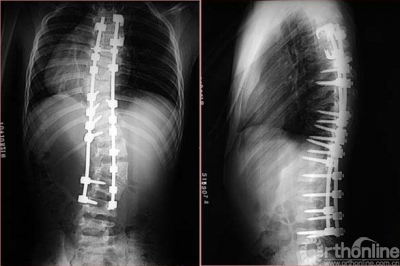

14岁女性患儿,青少年特发性脊柱侧凸,术前术后X线片及外观对比